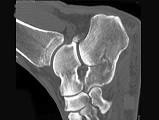

男,36岁,从高处摔下,足部受伤,结合图像,最可能的诊断是?(?)A.距骨骨折B.跟骨骨折C.骰骨骨折D.舟状骨骨折E.楔骨骨折

问题 男,36岁,从高处摔下,足部受伤,结合图像,最可能的诊断是?(?)

选项 A.距骨骨折 B.跟骨骨折 C.骰骨骨折 D.舟状骨骨折 E.楔骨骨折

答案 B